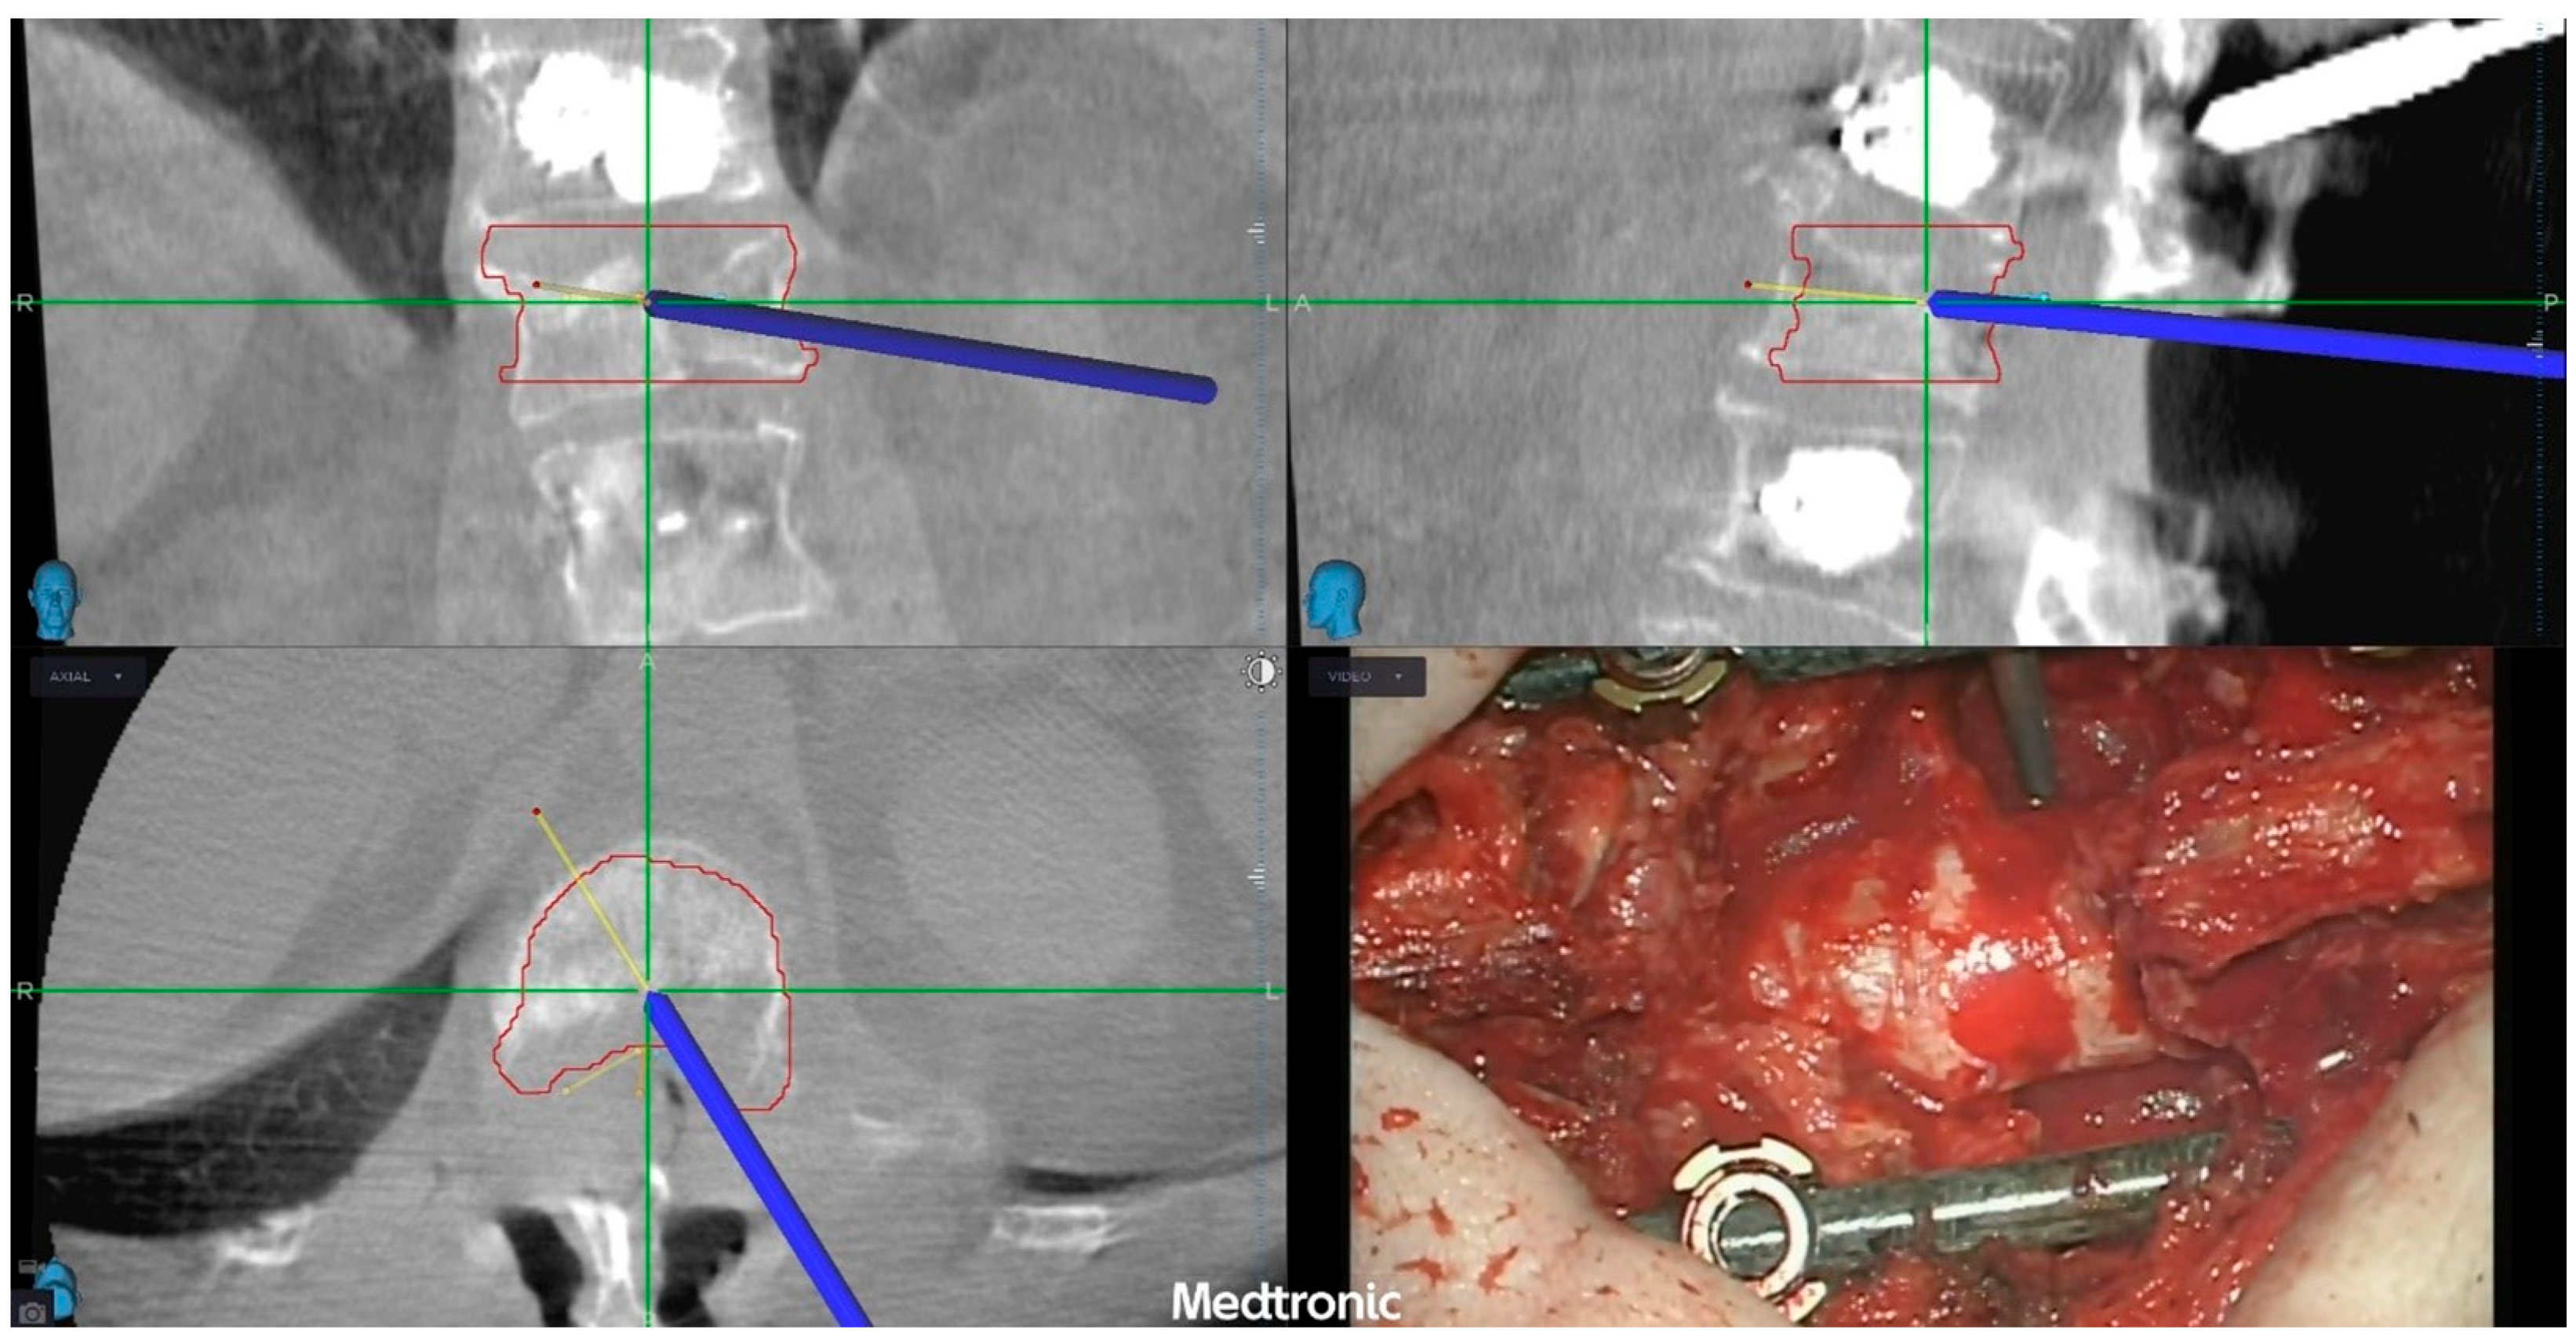

2.2. Pre-Operative Planning and Treatment Strategy

2.5. Post-Operative Course and Outcome